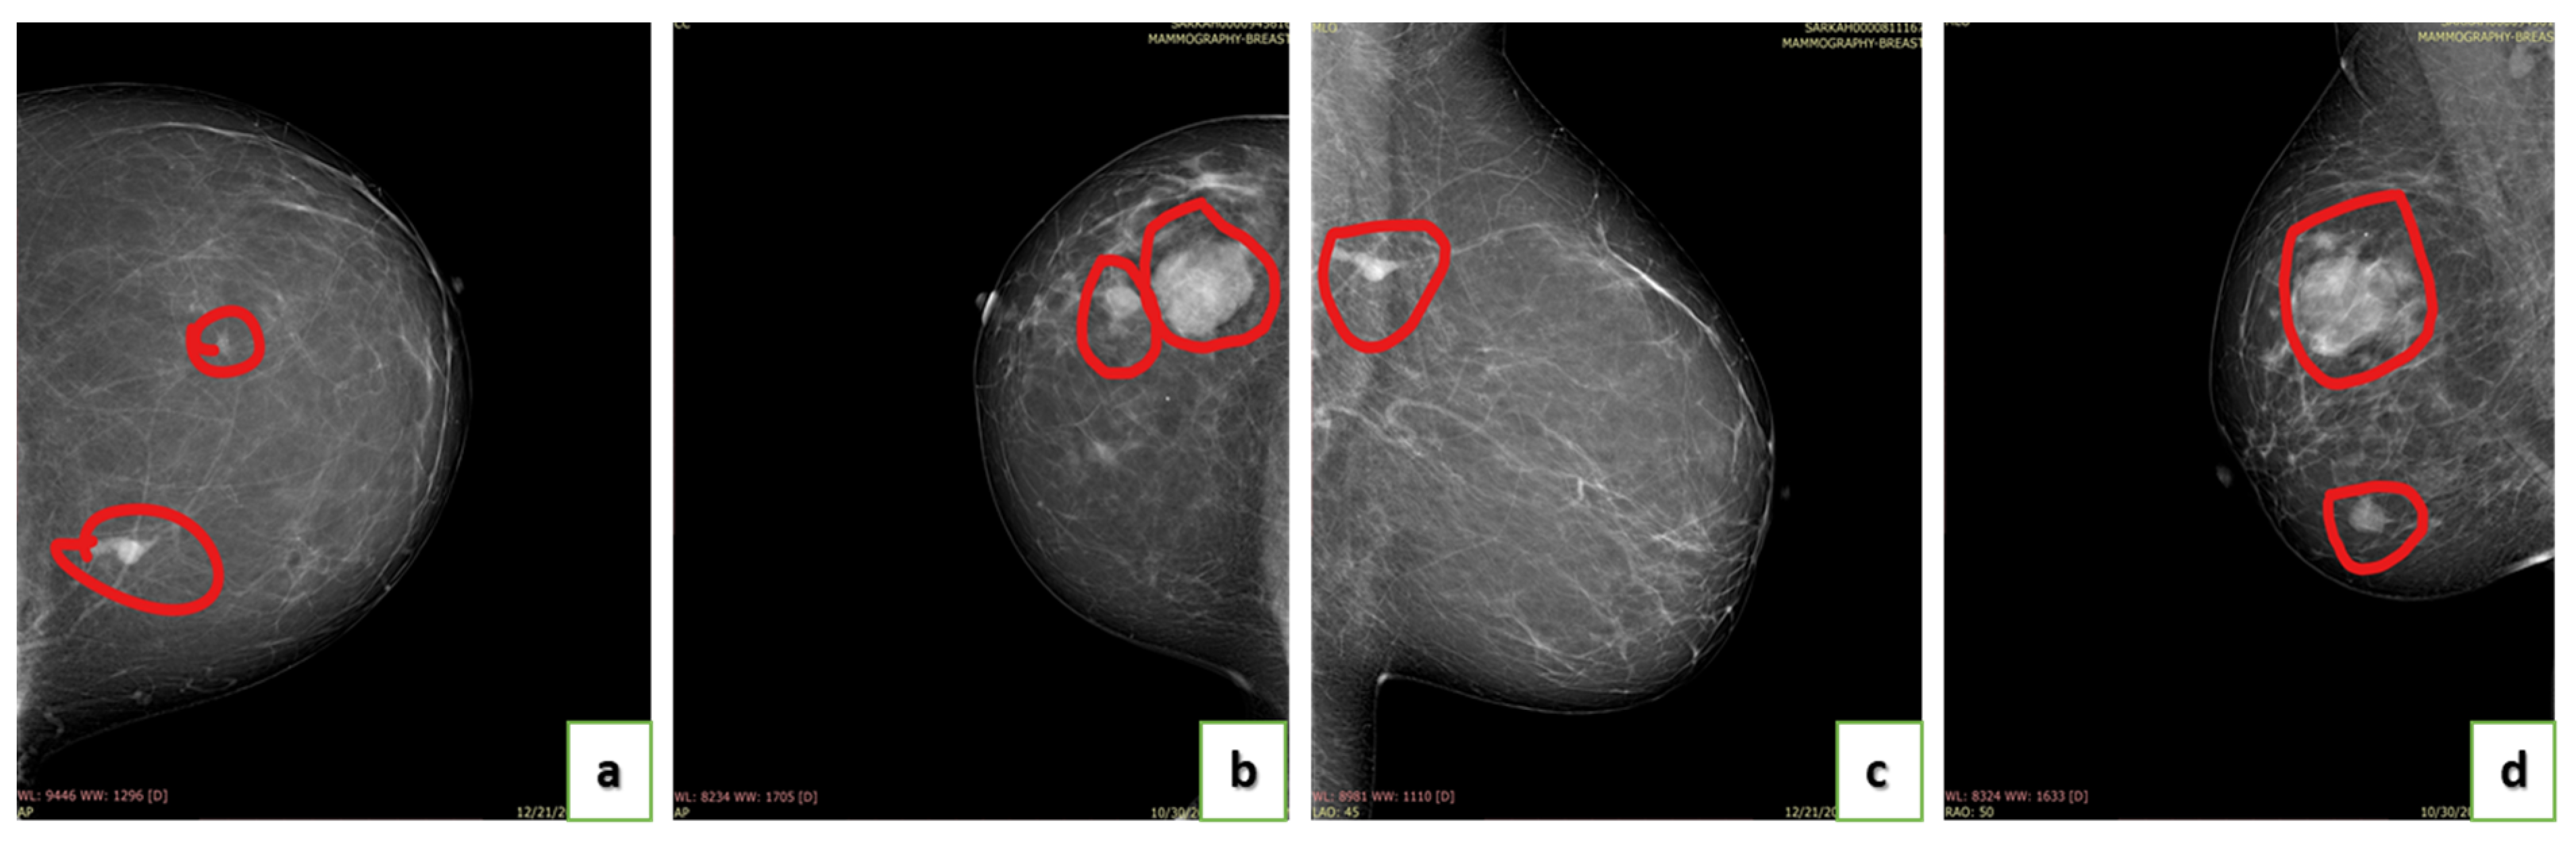

4.2. Annotation of Images

4.4. Breast Density